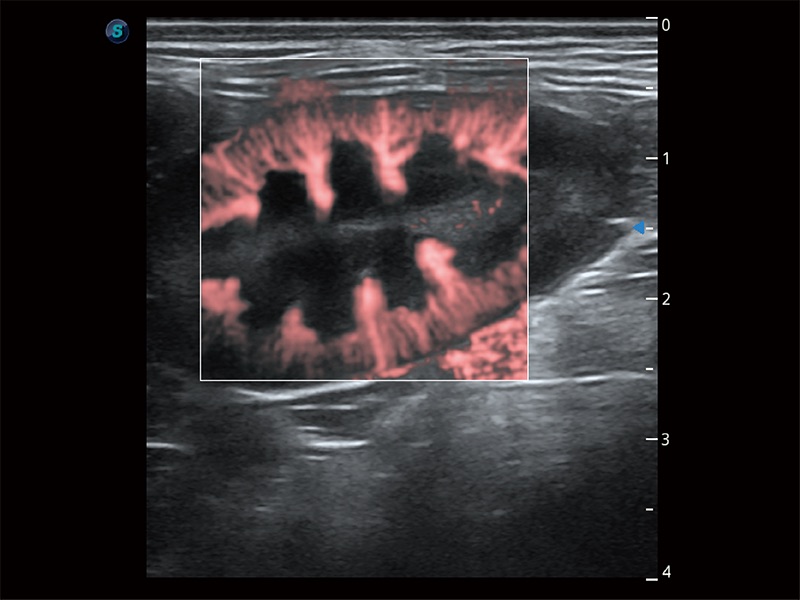

(犬)肠道

• Micro F 显微血流成像

极大提升超低速微细血流的检出能力,同时更精准地滤除软组织和超声信号,为兽用医生提供以往无法通过常规血流获得的疾病诊断信息。